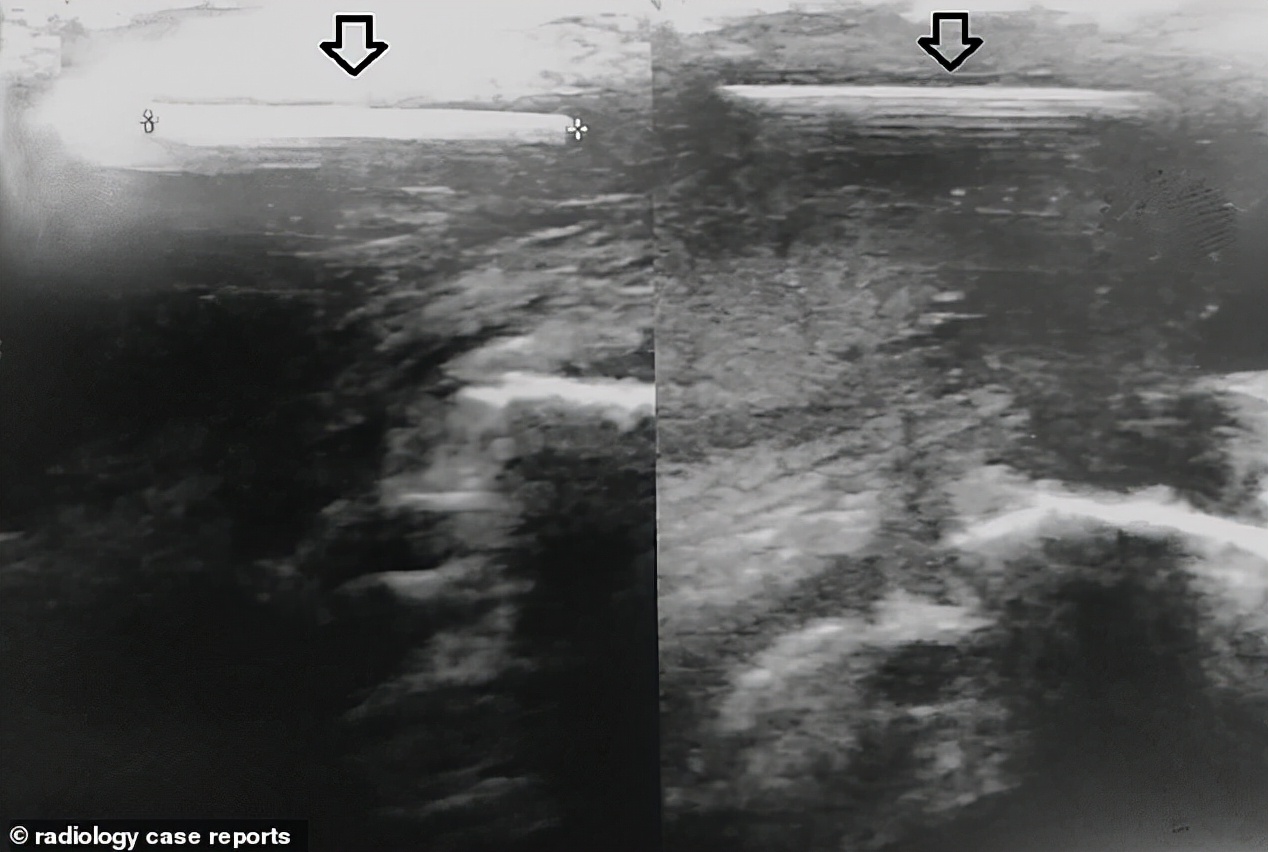

根据外媒《DailyMail》的报导,意大利一名27岁的工人在工作的时候不小心用钉枪打中自己的*体下**,1.8公分的钉子就这样插了进去,他痛倒在地被紧急送往医院治疗,但医生左翻右翻就是没看见有明显的伤口,还好泌尿科医生用超声波检查,才终于确认了钉子的位置,手术将它取出。

医生解释,因为钉子刚好卡在*体下**交界处,钉子又非常细所以伤口从外观看并不明显,所以一开始才会找不到。还好功能没有受到永久性的伤害,手术后隔天工人已经顺利出院。